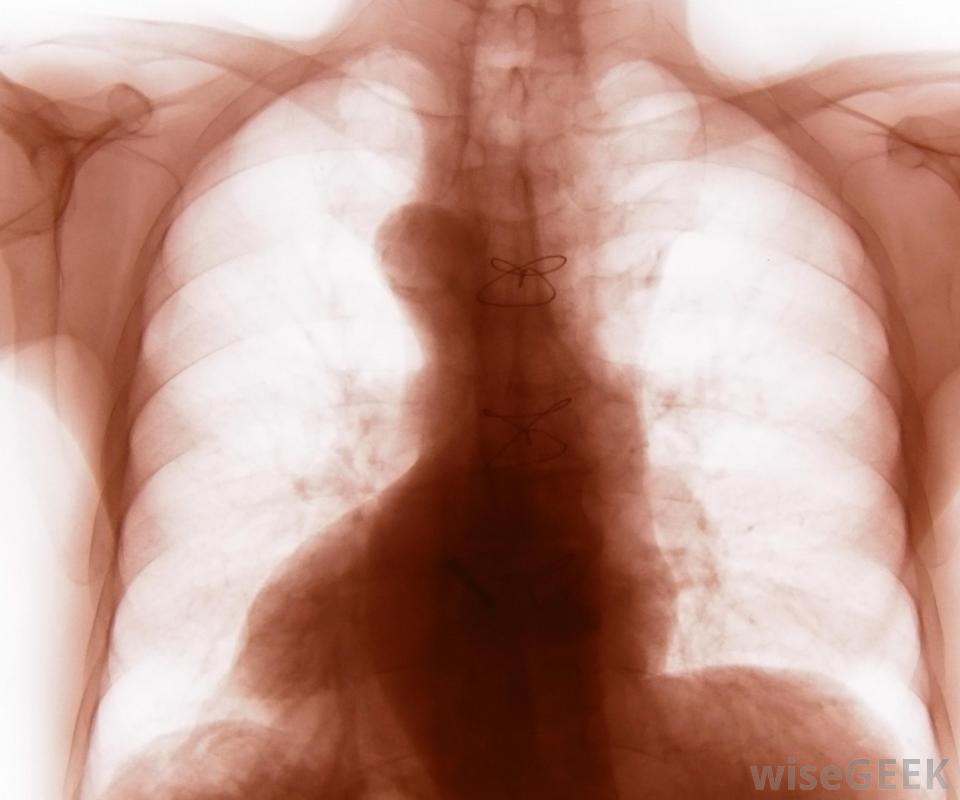

胸廓也被稱為胸腔。它由12對肋骨組成,通過12根椎骨連接到身體后部,胸椎是脊椎的一部分,位于頸椎或頸部的正下方。保護心臟、肺等重要器官,肝臟和胃是胸腔的一個非常重要的功能上部10對肋骨連接在身體前部,或前部。由于上部的7對肋骨圍繞側面朝前彎曲,每根肋骨都會遇到一塊薄薄的軟骨,這是一種非常堅韌但柔韌的組織。軟骨延伸到它與胸骨相連的地方,通常稱為胸骨胸腔包括12對肋骨,胸骨和12個椎骨。第八、第九和第十對也環繞在身體前部,但是連接到胸骨的軟骨是共享的,而不是單獨的一塊,第11對和第12對肋骨沒有前部附著物,這就是它們通常被稱為"浮動"肋骨的原因胸前胸腔的插圖和X光片可能只顯示第11對肋骨的一部分,而第12對肋骨往往很短,除了從身體的側面或背面看,它根本看不出來。手術時有時需要切開胸骨才能進入胸腔。肋骨與胸骨相連的肋軟骨阻止了整個胸腔的形成骨骼。這一點很重要,因為呼吸依賴于胸腔的擴張和收縮,而骨骼太硬,無法滿足胸腔內呼吸所需的靈活性。胸腔的形狀被稱為籠子,因為它包圍了身體的大部分軀干和肋骨對制作類似于籠子的鋼筋外觀。第12對肋骨可能在X光片上看不到外行人士不應期望能夠觸碰到漂浮的肋骨對或構成胸腔一部分的肋軟骨。肋骨任何部分的骨折都可能導致極度不適和胸腔器官損傷例如,汽車事故可能會導致一個人的胸部突然受到方向盤的強力擠壓,導致一根或多根肋骨骨折,可能刺傷心臟、肺、肝臟或胃,導致內出血可能進行胸部影像學檢查以診斷胸部損傷,除了休息、冰和非甾體抗炎藥之外,很少有治療方法可用。在心肺復蘇過程中實施胸部按壓可能會導致肋骨骨折。